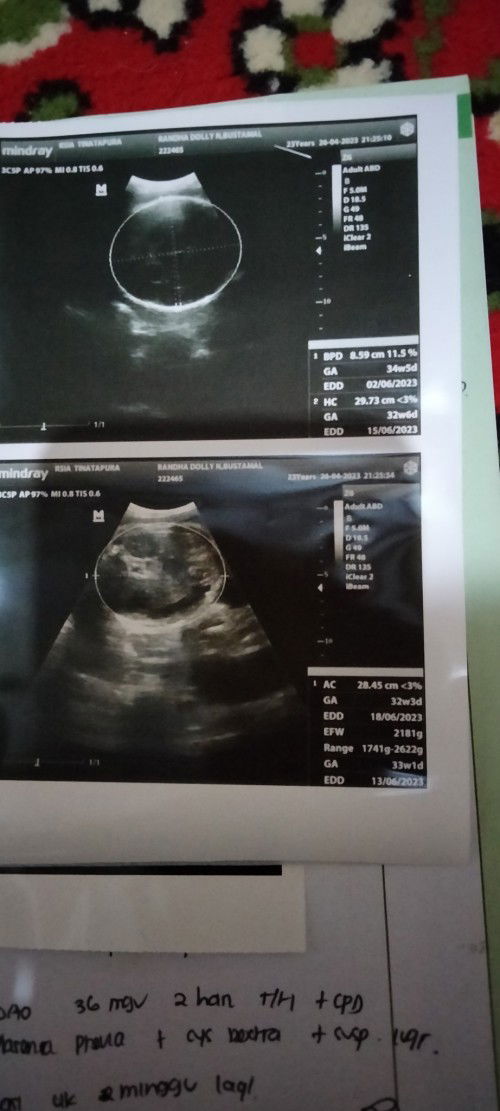

bunda ini#bantusharing #firstmom usia kandungan ku yg bener brp yah? yg atas atau bawah? tp dokternya jelasinnya klo usia kandungan ku itu udh 36 minggu 2 hari sdgkan itu ga ada diantara hasil USG atas dan bawah.. tolong dong bund jawabannya 🥹